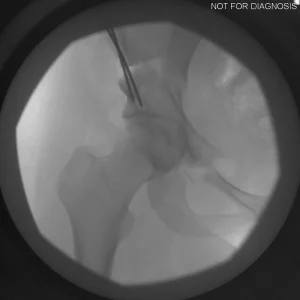

The Surgery

• PAO surgery typically takes 2-4 hours

• It is performed under general anesthesia

• Several controlled bone cuts are made around the hip socket

• The socket is repositioned and fixed with screws

• The hip joint itself is preserved